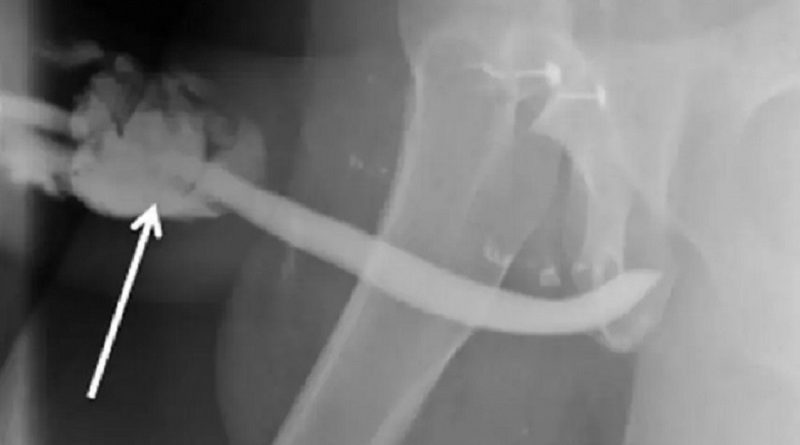

(Foto:Reprodução / International Journal of Surgery Case Report ) – Caso foi registrado na Tanzânia e o paciente, que não foi identificado, precisou passar por uma cirurgia de emergência

O paciente passou por uma cirurgia de emergência em um hospital de Kilimanjaro. Nos relatos dos médicos, a fratura teria deixado o pênis semelhante a um balão. No entanto, a recuperação foi rápida. Após três dias no hospital, o homem teve alta. Em casa, ele precisou usar um cateter por quase três semanas. Depois de seis meses o homem foi a uma consulta médica e disse que já havia retomado a vida sexual sem dificuldades. Apesar do pênis não ter ossos, os médicos usaram o termo “fratura” para definir a chamada ruptura da túnica albugínea, que é o tecido fibroso que mantém o sangue em circulação durante o momento de ereção. Para os médicos, a fratura também pode acontecer durante uma ereção noturna ou em uma masturbação.